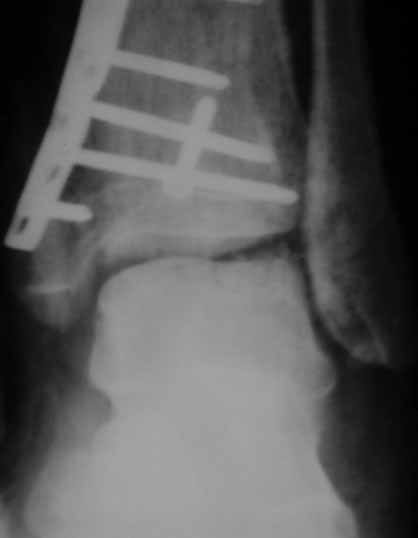

Извиняюсь пропал - оперировал "пилон". В форуме не хотел обсуждать финансовые возможности пациента. Потянул комбинированную пластину. Опыт общение с пластиной "крест" есть - не очень понравилось - слишком много места занимает, даже с учетом обрезаний лишнего. Сделал доступ огибающий медиальную лодыжку спереди. В переднем крае оказался достаточно крупный отломок - удалось зафиксировать винтом. Дефекта кости не оказалось.